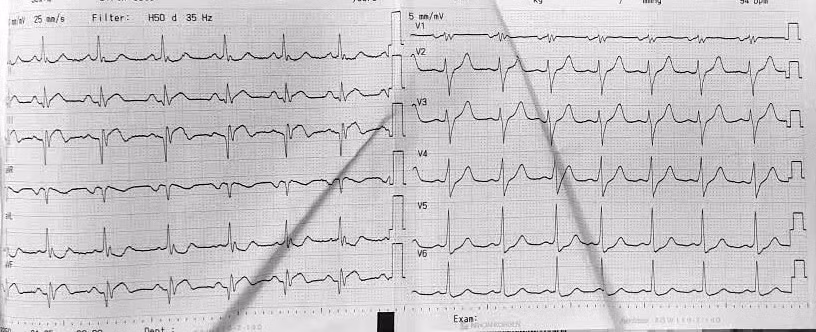

Điện tim bệnh nhân Q. trước mổ bình thường. Ảnh BV

Nhịp tim bất thường trên điện tâm đồ của bệnh nhân Q. sau phẫu thuật. Ảnh BV